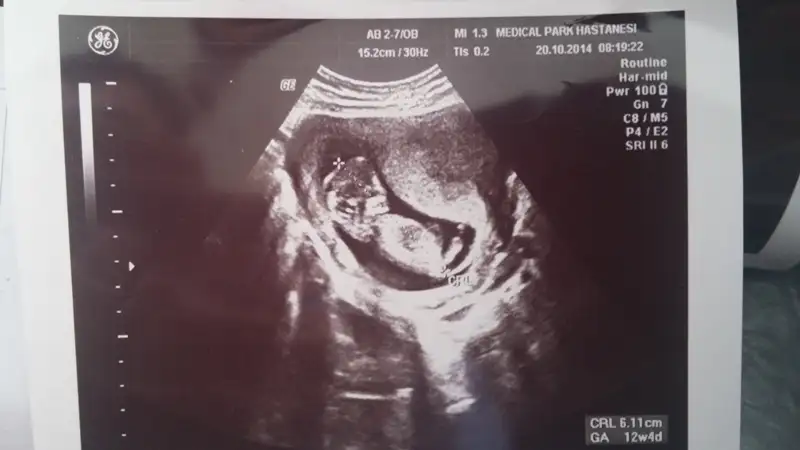

% 90 erkekArkadaşlar cinsiyet yorumu yapabilecek var mı? Lütfen yardım !!

Canim daha senin minnosun bacaklari bile tam cikmamis en iyi 12 ve 13 .haftalarda anlasilabiliyor:)Cevap verecek kimse yok mu![]()

Tesekkur ederim :))Canim daha senin minnosun bacaklari bile tam cikmamis en iyi 12 ve 13 .haftalarda anlasilabiliyor:)